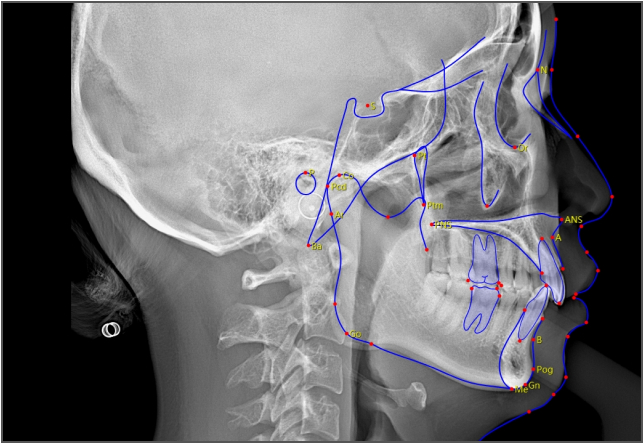

AI 加持,事半功倍 兰台医令的阅片软件包含 AI 神经管绘制、AI 气道分析、AI TMJ分析、AI 牙弓曲线、AI 正畸头影测量等智能图像处理功能,可大大提高诊断效率,实现更好的医患沟通,让医生事半功倍。